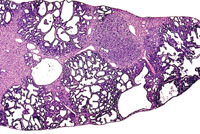

Areas of ductular formation and bile duct proliferation can be extensive in the livers of 3-week old AL-TAg x AL-myc mice.

By 4-weeks of age much of the liver is replaced by areas of ductular formation, cholangial neoplasms, and hepatocellular neoplasms in AL-TAg x AL-myc mice.